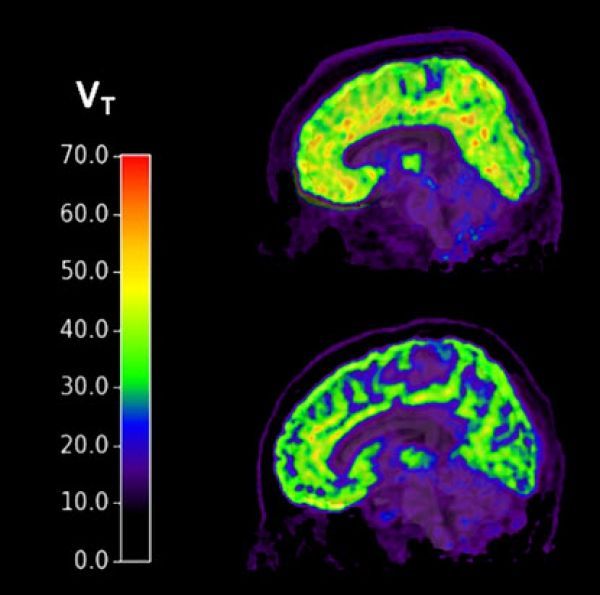

Researchers used PET imaging to measure levels of metabotropic glutamatergic receptor 5 (mGluR5) — which has been implicated in anxiety and mood disorders — in individuals with PTSD and major depressive disorder. They found high levels of mGluR5 in the PTSD group with current suicidal thoughts. They found no such elevated levels in the PTSD group with no suicidal thoughts or in those with depression, with or without current suicidal thoughts.

Image: Brains of individuals with PTSD and suicidal thoughts (top) show higher levels of mGluR5 compared to healthy controls (bottom).  CREDIT: Yale University